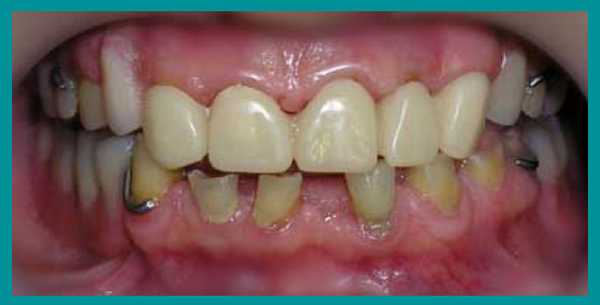

5 этап лечения

Когда необходимая высота прикуса была достигнута, были изготовлены металлические корневые вкладки. Далее были созданы бюгельные протезы на кламмерах с использованием металлокерамических коронок в виде опорных зубов.

После фиксации металлокерамических коронок на постоянный цемент, коррекции и установки бюгельных протезов на кламмерах, пациент получил рекомендации по уходу за зубными протезами и проведению личной гигиены полости рта. План лечения был выполнен. Рекомендовано профилактическое посещение стоматолога каждые четыре месяца.

Итог лечения

От начала лечения и до его завершения прошло больше года. В итоге пациент получил эстетичные и очень функциональные зубы, исчез психологический дискомфорт. Одновременно была решена проблема неправильного прикуса, восстановлена работа височно-челюстного сустава.